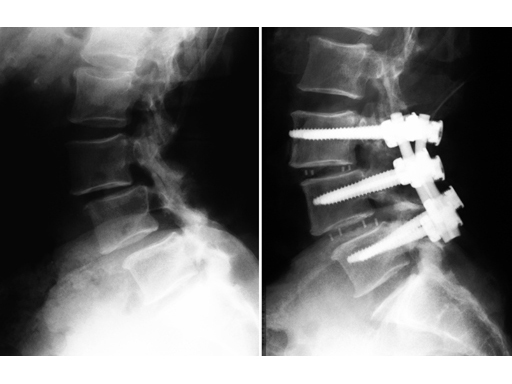

64-year-old woman, lateral, pre- and postoperative x-rays.